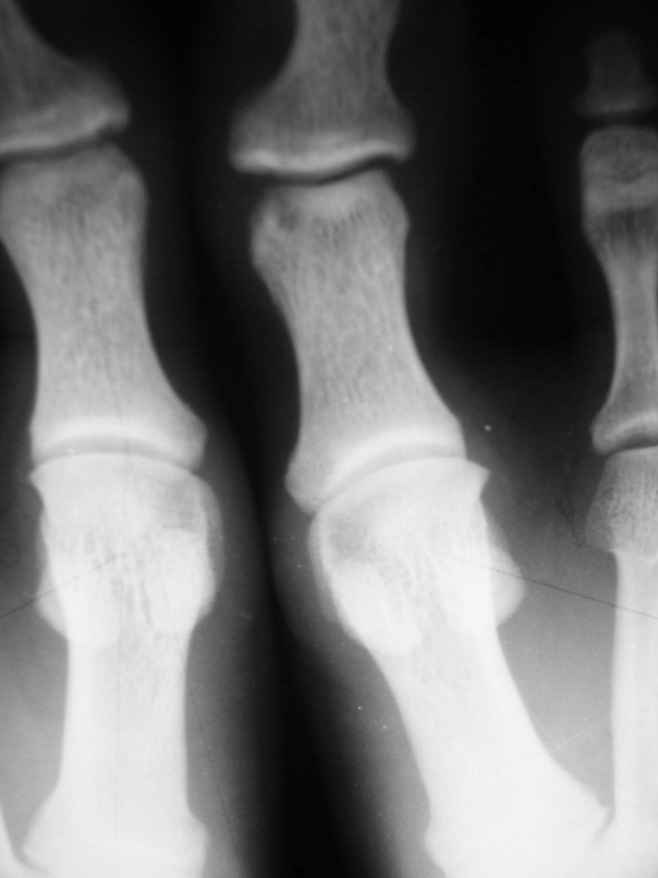

1-Пациент Х.18лет, аневризмальная костная киста малоберцовой кости и основной фаланги I пальца левой стопы (Рис. 1,2).

На представленных снимках рентгенологическая картина АКК не соответствует - в первом случае рентгенологическая картина (учитывая центральное расположение ) более соответствует солитарной костной кисте м.берц. кости, а в фаланге - кистовидная перестройка, во втором случае - гигантоклеточная опухоль